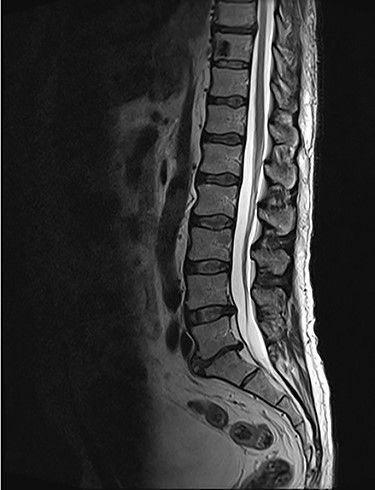

Spinal images are presented in Figs 1–6. Cross-sectional imaging revealed no other neoplastic lesion. He received dexamethasone 10 mg bolus then 4mg four times daily with appropriate proton pump inhibitor coverage. Due to no distinguishable major arterial feeder upon review of the imaging jointly with the neuroradiologist, pre-operative embolization was not attempted. The following morning, he underwent posterolateral right costotransversectomy, ligation of the ipsilateral T4 nerve root, T4 vertebrectomy and insertion of an expandable titanium cage with T1–T7 pedicle screw fixation (Figs 7 and 8). Post-operatively his pain improved to VAS 2/10 and motor power in his left lower limb improved to MRC grade 4/5. The patient was discharged home Day 10 post-admission with physiotherapy.

Sagittal T2-weighted magnetic resonance image (T2W MRI) with T4 metastatic epidural spinal cord compression (MESCC) and a synchronous T10 lytic lesion.